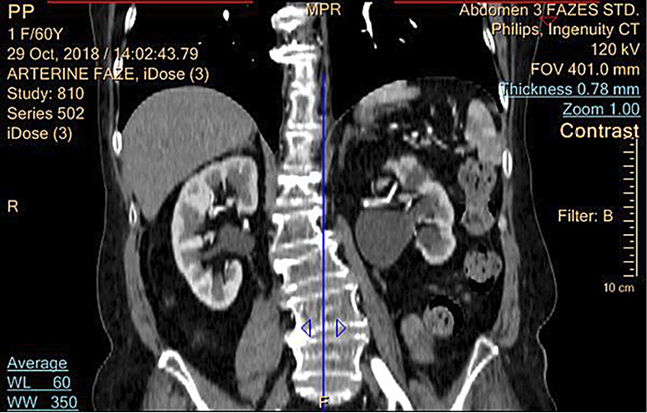

Atlikus KT (2018-10-29) – kairiojo inksto ryški hidronefrozė (iki 34 mm), dešinėje geldelė praplėsta iki 12 mm; abipus šlapimtakiai nepraplėsti (žr. 2 pav.).

2 pav. Pacientės inkstų KT prieš operaciją